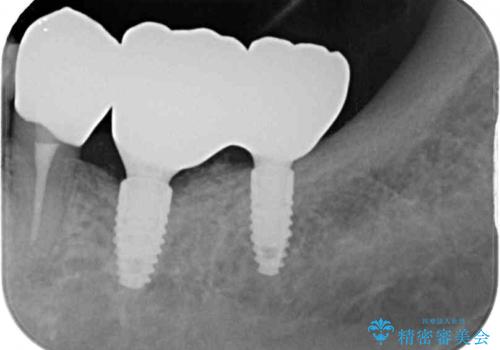

- 一度治療を終えたものの、奥歯へインプラントの追加を希望された患者様です。

最後臼歯部にインプラントを1本追加埋入し、2歯連結のクラウンにて補綴治療を行うこととしました。